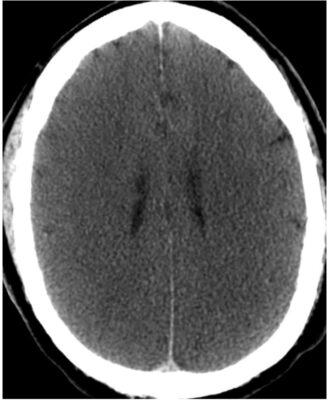

- Các não thất có thể bị đè ép (Hình 15).

- Đánh giá CT não ban đầu trong trường hợp khẩn cấp tập trung vào việc có (a) hiệu ứng choán chỗ (mass effect) và (b) máu hay không.

- Để xác định xem có hiệu ứng choán chỗ hay không, hãy tìm sự dịch chuyển hoặc đè ép của các cấu trúc chính so với vị trí bình thường của chúng bằng cách phân tích vị trí và hình dáng của các não thất, bể đáy và các rãnh não.